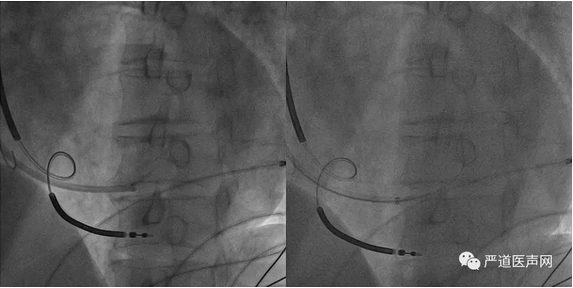

寻找CS开口方案一:传统方法

● 使用冠状窦电生理标测电极和左室递送系统一起寻找冠状窦口,常用在LAO下,以三尖瓣和脊柱作为标记来进行

LAO

寻找CS开口方案二:Amplaz导管+超滑导丝

● 借助Amplatz导管的形状和支撑,泥鳅导丝探索,推送外鞘管进入CS时注意同轴性